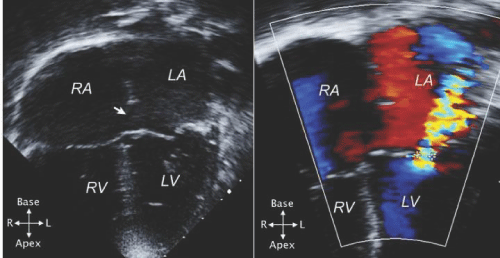

| Figure 9: A - An echocardiogram in apical 4 - chamber view in a patient with ASD1 (arrow). The defect is just above the closure plane of the AV valves. B - Color Doppler exam in the same view showing mitral regurgitation (++), most likely through the cleft in the anterior mitral leaflet. LA - left atrium; LV left ventricle; RA - right atrium; RV - right ventricle. (Reprinted from Valente et al. [11] with permission). |